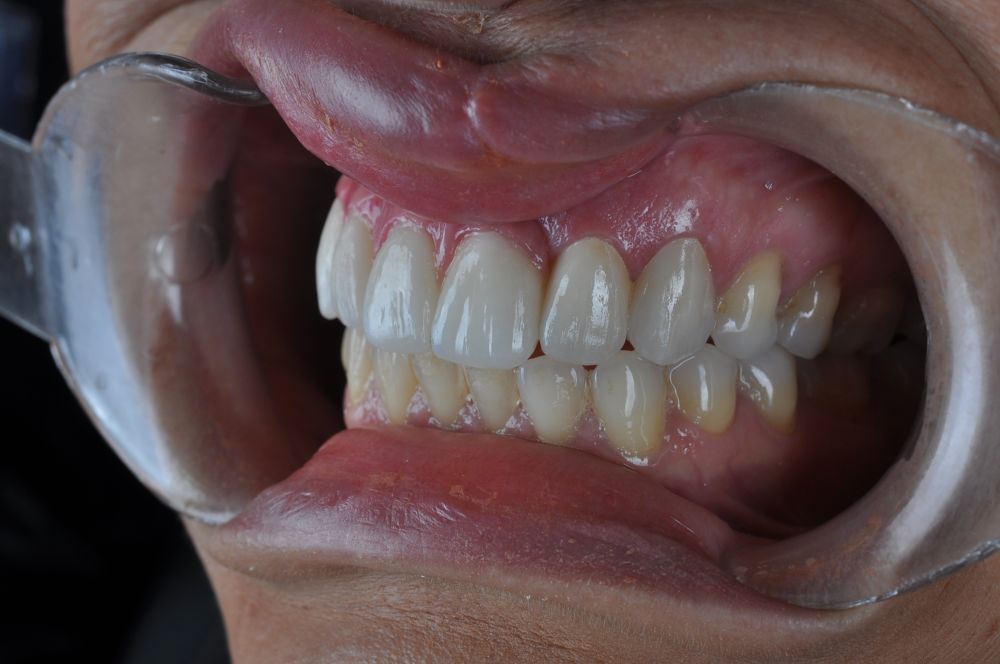

Para la fabricación de las estructuras, se eligió el óxido de zirconio monolítico como material restaurador sobre interfases metálicas en el puente implantosoportado, y coronas de óxido de zirconio monolítico en los dientes tallados previamente (1.7, 1.6, 2.2 y 2.3). Se tomaron impresiones de cubeta abierta con silicona de adición pesada y fluida (Zhermack Elite HD, Gmbh). Se realizó una prueba de pasividad analógica y el resto del proceso se confeccionó de manera digital, por lo que se hicieron pruebas estéticas de dientes impresas en 3D sobre interfases metálicas, para hacer todos los ajustes de función y estética previos al fresado del zirconio monolítico (Figuras 11, 12 y 13).

El día de la colocación de las estructuras, se arenó el interior de las coronas dentosoportadas con óxido de aluminio de 50 m y fueron cementadas con cemento de resina Multilink Ò. El puente implantosoportado se atornilló al torque indicado (20Nw) (Figuras 14, 15, 16 y 17).

Las impresiones analógicas y el posterior flujo digital permitieron una correcta planificación protésica. Las estructuras definitivas, confeccionadas en óxido de zirconio monolítico sobre interfases metálicas de titanio, mostraron una adecuada adaptación pasiva tanto clínica como radiográficamente. La prueba estética permitió ajustes oclusales y funcionales mínimos, optimizando el resultado final.

En enero de 2021, el puente implantosoportado fue atornillado con un torque controlado (20 Nw), y las coronas dentosoportadas cementadas con éxito. La paciente refirió una notable mejoría en la función masticatoria, fonación y estética facial, manifestando un alto grado de satisfacción.

En el seguimiento a 4 años tras la colocación de la prótesis definitiva, no se observaron complicaciones mecánicas ni biológicas. La paciente continúa libre de enfermedad y con una correcta adaptación al tratamiento rehabilitador implantosoportado (Figura 18).